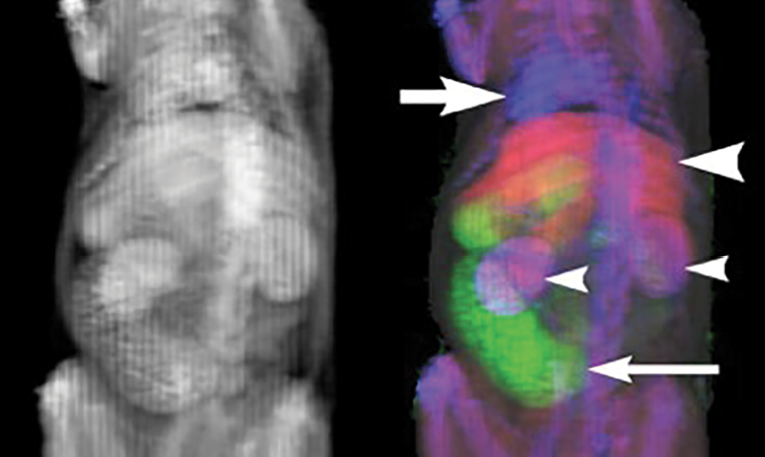

These new generation contrast agents, instilled into different bodily compartments, promise to provide high spatial resolution, co-registered images of complex anatomy with a single pass of the CT scanner without added radiation dose or imaging time (See Figure 2). Such contrast agents promise to provide intuitively simple displays of complex anatomy at MECT imaging.

An analogy for understanding the value of multi-contrast MECT is PET/CT: PET and CT are each valuable scans, and the two combined is synergistic. Likewise, each added contrast agent color for multi-contrast MECT promises synergistic benefit. But unlike PET/CT, which doubles the dose over that of either PET or CT alone, MECT does not require additional radiation above that of a standard CT scan. MECT also provides perfect image co-registration of the different contrast agents because the images are derived from a single MECT scan.

Figure 2: Future advances in multi-energy CT (MECT) enhanced with multiple color contrast agents will make complex abdominal anatomy more intuitive to evaluate. (Left) An oblique coronal conventional average intensity image of a rat CT scan shows multiple contrast-enhanced thoracoabdominal organs in the traditional gray scale. The differentiation of organs is by educated guesswork and is our current state-of-the-art. (Right) The same MECT images are presented in with three different colors. Organ differentiation is now simple and intuitive. Intravenous contrast agent (blue area, large arrow) opacifies the cardiac chambers and vessels, distinct from the hepatic contrast agent (red area, large arrowhead) and bowel contrast agent (green area, small arrow). Combined vascular and hepatic contrast agents (purple area, small arrowheads) opacify the kidneys. Further automated image processing, such as to define organ boundaries and quantify organ volume, is greatly simplified. Image interpretation is made more intuitive for humans and simpler for machines. Disclaimer: No U.S. Food and Drug Administration approved color MECT contrast agents are currently available.

Images courtesy of Yuxin Sun, MS, and Jack Lambert, PhD